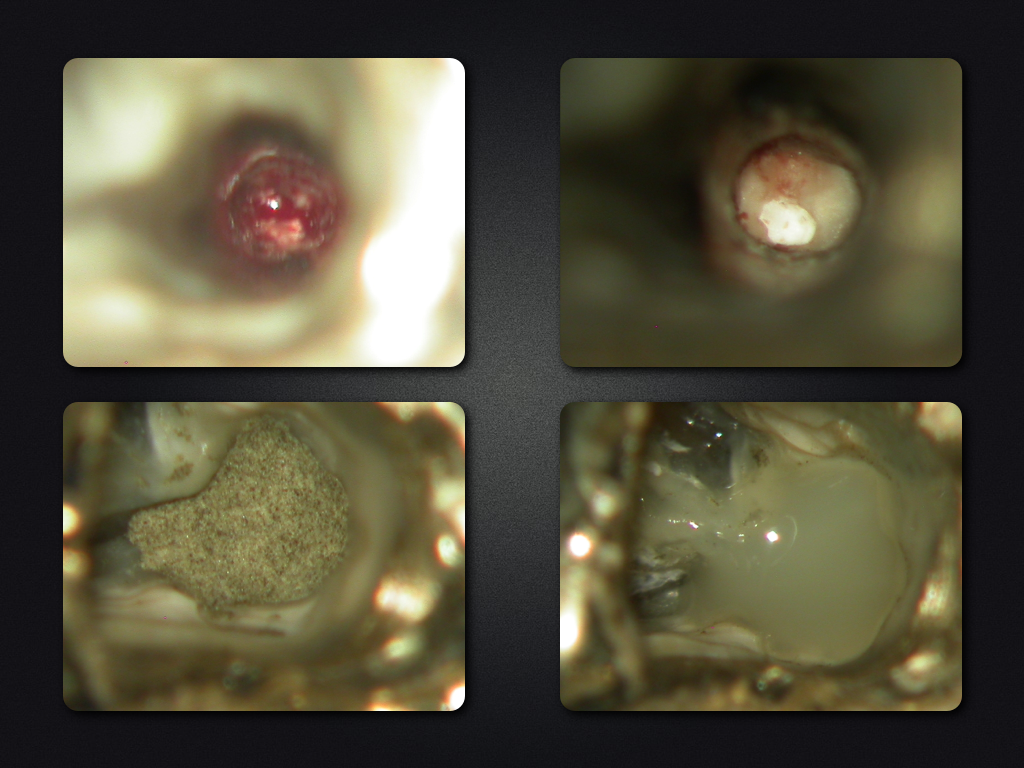

2D vs. 3D (XXV)